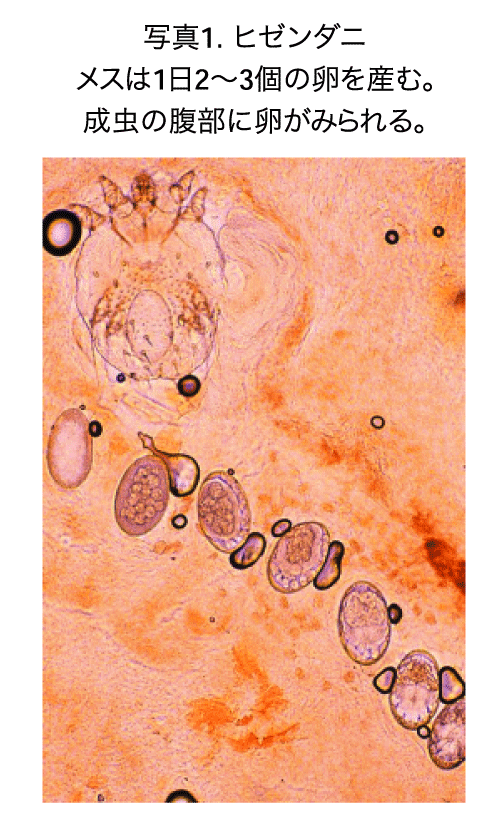

ヒゼンダニの大きさは雌成虫で体長約400μm、体幅約325μmで、卵形、円盤状で(写真1)、肉眼ではほとんど見えない。雄は雌よりさらに小型である。卵→幼虫→若虫→成虫と約2週間で成熟する。幼虫、若虫、雄成虫は人の皮膚表面を歩き回るため、皮膚同士の接触によって感染する。また、皮膚内に掘った穴や毛包内に隠れていたりするため、ダニの寄生部位を特定するのは難しい。皮表を歩き回っている雄は雌を探し、交尾する。交尾後の雌成虫は、角質層に特徴的な疥癬トンネルを掘り進みながら、4~6週間にわたって1日2~3個ずつ産卵し続ける。卵は3~4日で孵化し、幼虫はトンネルを出てはいまわる。